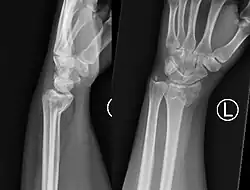

Two views should be obtained: AP and lateral.

PA radiography will look very similar to a Colles' fracture, with a fracture along the distal metaphysis of the radius (can be shortened or comminuted). Lateral radiography will demonstrate volar angulation / displacement of the fracture.[6]